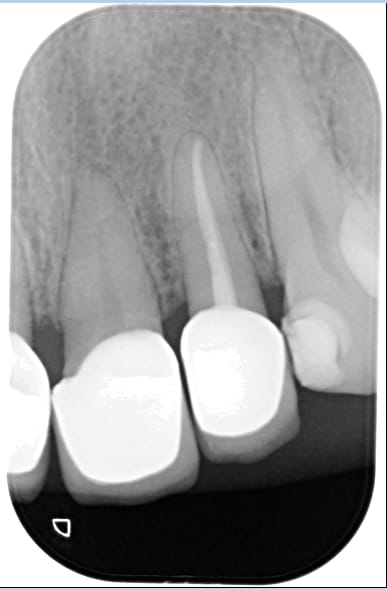

le meme genre de cas avant et apres le jour de la pose

plus tard la papille s'est recrée .